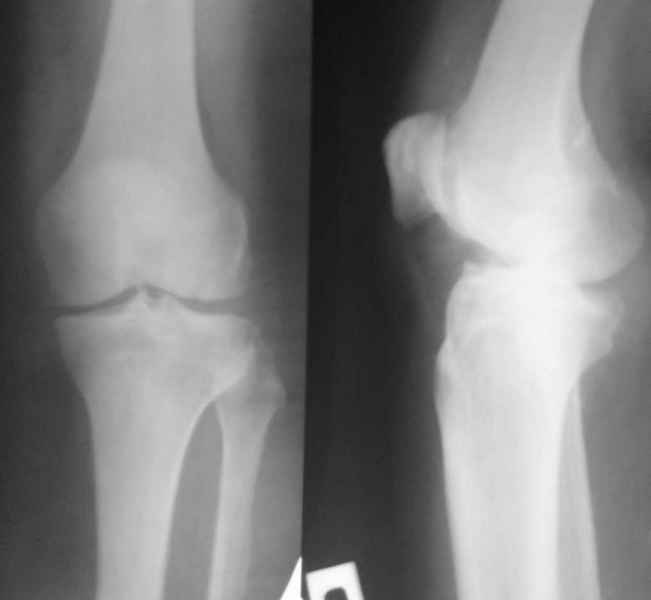

Уважаемые коллеги, Прошу совета. В феврале 2007 года пациентке выполнено эндопротезирование коленного сустава.

13/02/07 |  25/07/07 |  дек. 07 |  25/06/08 |  14/01/09 | Через 1 месяц после операции объем движений 90 градусов, через 2 месяца 60, через 3 - 40, через 5 - качательные движения.

Уважаемый Андрей, действительно по снимку до операции сустав кажется сохранным. Но этой пациентке за несколько месяцев до операции была выполнена артроскопия, задокументировано отсутствие хряща на суставных поверхностях внутренних мыщелков бедренной и б\б костей. Этот снимок сделан без нагрузки и поэтому создается впечатление "сохранного сустава". Если бы был сделан снимок до операции с нагрузкой, вашего вопроса не было бы.

Надо было протезировать такой сустав? Может быть у меня на компьютере не очень хорошее разрешение, но мне показалось, что сустав еще сохранный и можно было полечить более консервативными методами - артроскопия, хондропротекторы. Хотя я знаю, Александр Николаевич, Ваше отношение к ним.